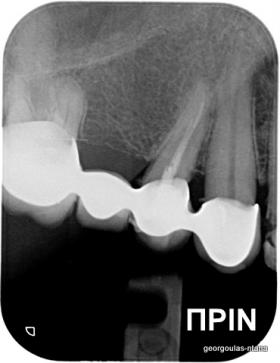

ΟΛΙΚΗ ΑΠΟΚΑΤΑΣΤΑΣΗ ΑΝΩ ΓΝΑΘΟΥ

Η ασθενής ήταν δυσαρεστημένη από την εμφάνιση των άνω δοντιών της. Ήθελε τα δόντια της να αποκτήσουν ομοιόμορφο, πιο λευκό χρώμα κ να αποκτήσει ένα πιο αρμονικό χαμόγελο με φυσική εμφάνιση. Λόγω των εκτεταμένων εμφράξεων σύνθετης ρητίνης στα πρόσθια δόντια, των εμφράξεων αμαλγάματος στα πίσω αριστερά δόντια αλλά και της υπάρχουσας γέφυρας στα πίσω δεξιά δόντια, και σε συνδυασμό με την επιθυμία της ασθενούς για φυσικό αποτέλεσμα αποφασίστηκε η τοποθέτηση ολοκεραμικών στεφανών στα δόντια της άνω γνάθου. Στη θέση του δεύτερου προγομφίου δεξιά τοποθετήθηκε εμφύτευμα. Πραγματοποιήθηκε περιοδοντική θεραπεία, ενδοδοντικές θεραπείες (απονευρώσεις) κ τοποθετήθηκαν ενδορριζικοί άξονες υαλονημάτων όπου κρίθηκε απαραίτητο. Σε όλη τη διάρκεια της θεραπείας η ασθενής ήταν καλυμμένη αισθητικά κ λειτουργικά με προσωρινές αποκαταστάσεις.